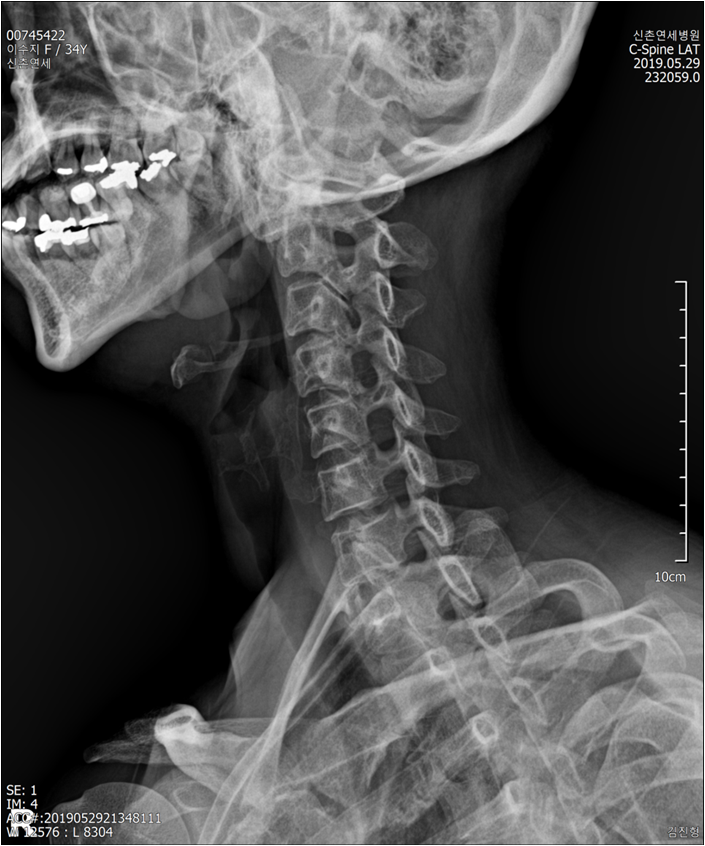

119에 실려 밤 12시가 조금 안된 시간에 신촌연세병원에 갔고 엑스레이를 찍었습니다. 일자목은 워낙 오래된 것이었고,등이 굽었다고 했습니다. 주사를 맞고 일단 퇴원하되 외래 진료를 오라고 했습니다. 다음날 광화문 자생한방병원에 갔고 MRI 촬영을 하였고 입원하라고했습니다. 하루에 2번씩 도수치료, 추나요법, 침치료, 물리치료, 약복용을 하였습니다. 4일을 그렇게 누워있는데도 나아질 기미는 안보이고일주일정도 더 입원을 하라는데 병원비가 300만원 정도였습니다. 너무부담이 큰데 몸은 너무 개선의 여지가 없고 답답해서 퇴원하겠다고 했습니다. 퇴원해서 주변에 디스크 지인들에게물어물어 각종 디스크 치료법을 알아보았습니다. 도수치료와 주사요법을 많이 추천받았는데 이미 받아봐도이건 답이 아닌 것 같아서 다른 방법을 시도해봅니다. 오랫동안 자가 수련을 하신 친척분이 집으로 오셔서마사지와 운동법을 알려주시기도 하고 소개받은 마사지 샵에서 병원에서 물리치료 하셨었다는 원장님께 마사지를 1번에 10만원씩 5회 정도 받았습니다. 인도우붓치료법을 배우신 또 나름 유명한 분도 소개받아서 역시 1번에 6만원씩 10번 정도를 받았습니다. 그 기간에 대상포진까지 같이 와서 비타민주사, 영양제를 몸에 때려 넣으며 지냈습니다. 그렇게 2달을 창업한 스튜디오는 방치한 채 여러곳에 돈을 뿌리며 통증을 해결하려고 방황하고 다니며 살았습니다.